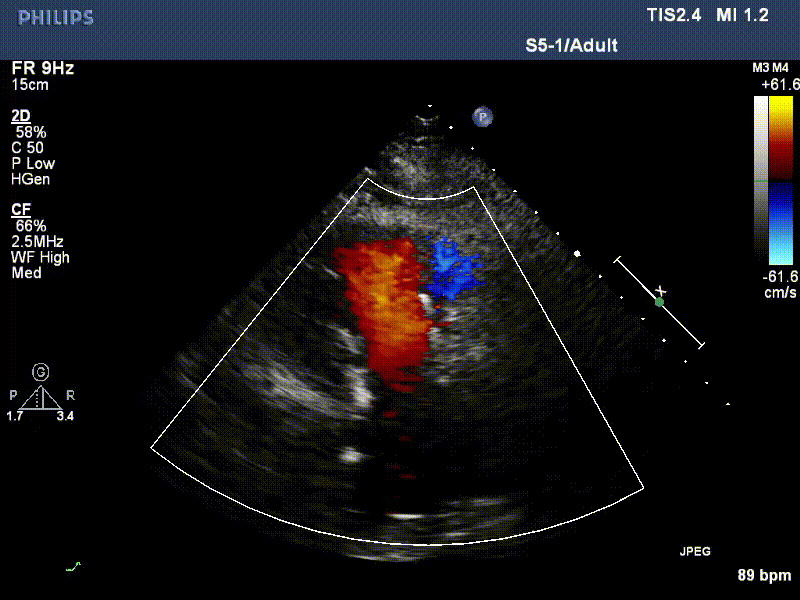

LuX-Valve Plus早期救治性臨床研究入組的首兩例患者均接受過二尖瓣人工瓣膜置換手術(shù),術(shù)前NYHA心功能均為Ⅲ級,極重度三尖瓣反

流并分別伴有房顫和房撲,高外科手術(shù)風(fēng)險。術(shù)前超聲提示,兩例患者下腔靜脈寬度分別為13mm和29mm,右房內(nèi)徑(上下徑和左右徑)分別為52×41mm和53×43mm,彩色多普勒顯示極重度三尖瓣反流,VCW分別為14×15mm和10mm。

1年前,兩例患者因難治性雙下肢水腫輾轉(zhuǎn)多家醫(yī)院尋求救治,考慮到兩例患者高齡、基礎(chǔ)疾病多、STS評分高,不適合傳統(tǒng)外科開胸手術(shù),葛均波院士及其團(tuán)隊周達(dá)新教授、潘文志教授、張源博士、陳莎莎博士、陳丹丹博士聯(lián)合心外科王春生、魏來主任,麻醉科繆長虹、郭克芳主任以及心超室的潘翠珍教授、李偉教授共同討論決定,采用我國創(chuàng)新器械LuX-Valve Plus經(jīng)血管三尖瓣置換系統(tǒng)為患者進(jìn)行手術(shù)。相較于第一代產(chǎn)品LuX-Valve,LuX-Valve Plus經(jīng)血管三尖瓣置換系統(tǒng)對輸送系統(tǒng)進(jìn)行了全面升級,實現(xiàn)了經(jīng)頸靜脈入路的方式,進(jìn)一步減小了手術(shù)風(fēng)險和對患者的創(chuàng)傷。目前隨訪1年心超結(jié)果顯示,三尖瓣極重度反流消失,人工三尖瓣瓣膜穩(wěn)定牢固,瓣葉活動度良好,右心室及下腔靜脈明顯縮小,心輸出量增加。兩位老人手術(shù)后沒有出現(xiàn)過胸悶氣促的癥狀,下肢水腫緩解,活動耐力提升,生活質(zhì)量也大為提高。

圖2 患者植入LuX-Valve Plus后,1年隨訪心超提示無三尖瓣反流